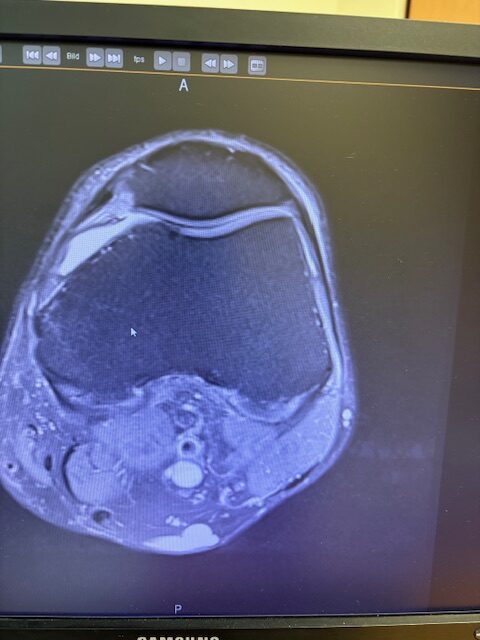

Ο ακτινολογικός έλεγχος (ακτινογραφίες/μαγνητική τομογραφία) ανέδειξε προχωρημένη οστεοαρθρίτιδα του έσω κονδύλου, με πλήρη διατήρηση του έξω διαμερίσματος και της επιγονατιδομηριαίας άρθρωσης. Με βάση αυτά τα ευρήματα, ο ασθενής ήταν ιδανικός υποψήφιος για μερική (μονοκονδυλική) αρθροπλαστική γόνατος.

Πραγματοποιήθηκε απεικόνιση και ψηφιακός σχεδιασμός της επέμβασης, ώστε να προσδιοριστεί με ακρίβεια το μέγεθος και η θέση των προθέσεων. Ο στόχος ήταν να αποκατασταθεί η φυσιολογική μηχανική του γόνατος, διατηρώντας ανέπαφα τα υγιή τμήματα της άρθρωσης, τους συνδέσμους και τους γύρω μυς.